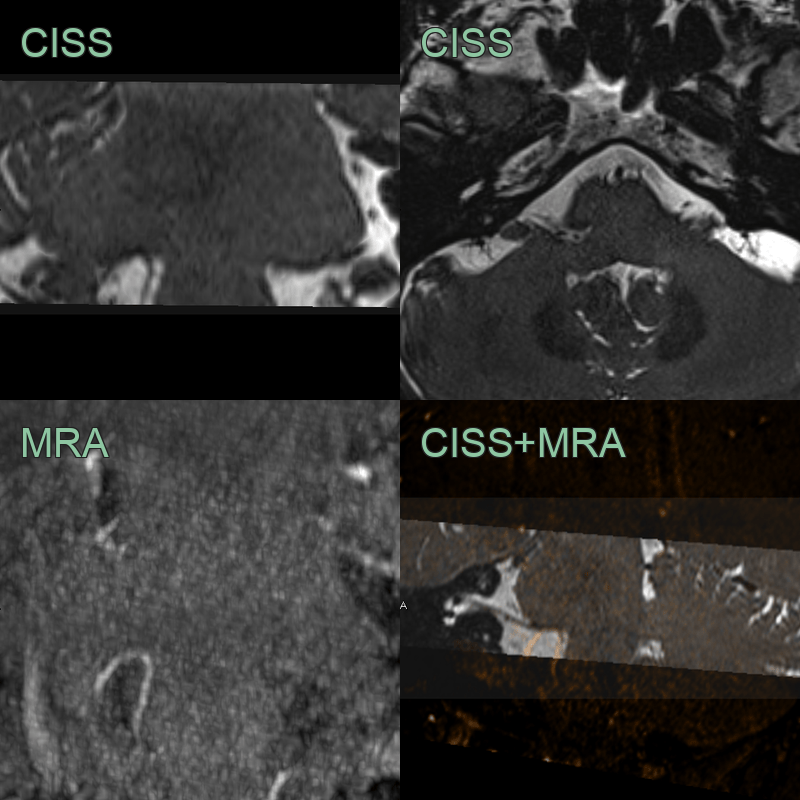

• A patient presenting with right hemifacial spasm has an MRI showing contact between the attached segment of the facial nerve and a superiorly looping PICA.